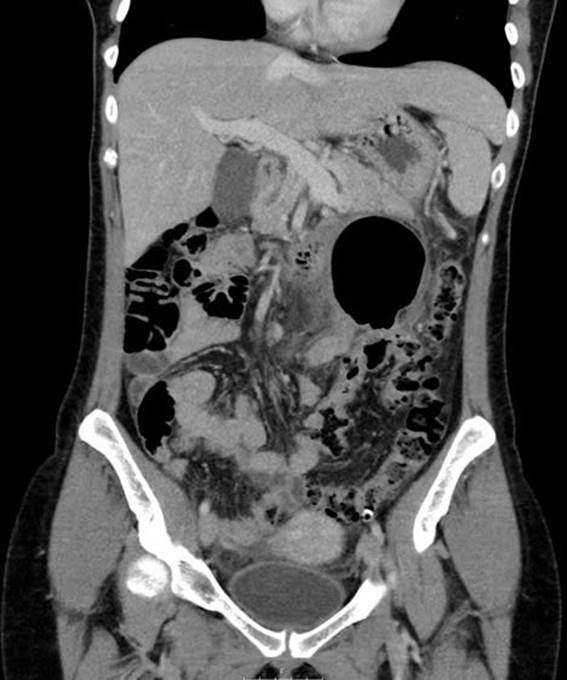

mostró una imagen de gas intraabdominal, similar a un globo. Se realizó una tomografía computada abdominal que informa la presencia de una “gran burbuja” aérea

en el hemiabdomen izquierdo sin poder concretar su origen (Fig. 1). Descartado el neumoperitoneo, se completó

Figura 1. Tomografía computada en la que se aprecia el “signo del globo”, una gran burbuja área de paredes finas, sin continuidad con la luz del colon.